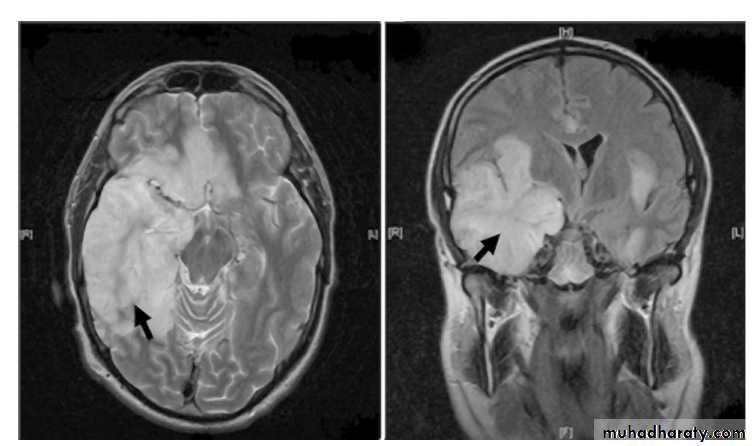

Magnetic resonance imaging is the imaging modality of choice, and is abnormal in 90% of patients (figure⇓).

Brain imaging both helps to support the diagnosis of herpes simplex encephalitis and to exclude contraindications to lumbar puncture. It typically shows unilateral or asymmetric bilateral high signal in the medial temporal lobes, insular cortex, and orbital surface of the frontal lobes (best seen with fluid attenuated inversion recovery (FLAIR) and diffusion weighted imaging (DWI)). These changes are not specific for herpes simplex.

Axial and coronal T2 weighted magnetic resonance images showing areas of hyperintensity (arrowed) corresponding to

oedematous changes in the temporal lobes and inferior frontal lobes with mass-like effect due to herpes simplex virus encephalitis. Reproduced with permission of Southampton General Hospital’s picture library